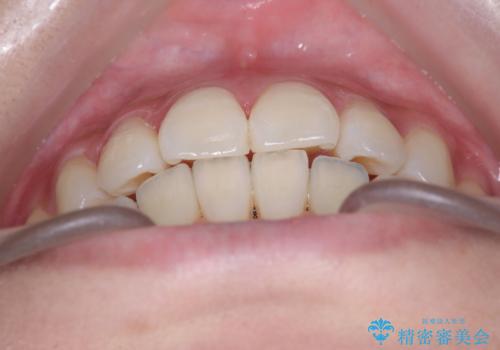

反対咬合を治したい。インビザライン

- 前歯の反対咬合を治したいことを主訴に来院されました。

インビザラインにて臼歯の遠心移動を行いながら、スペースを作り反対咬合を改善することができました。

反対咬合はインビザラインの方が治しやすい場合もあります。